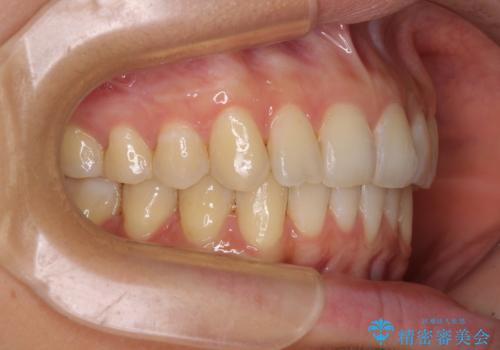

カリエールディスタライザーを併用したことで、確実かつ短期間で治療を終えることができました。